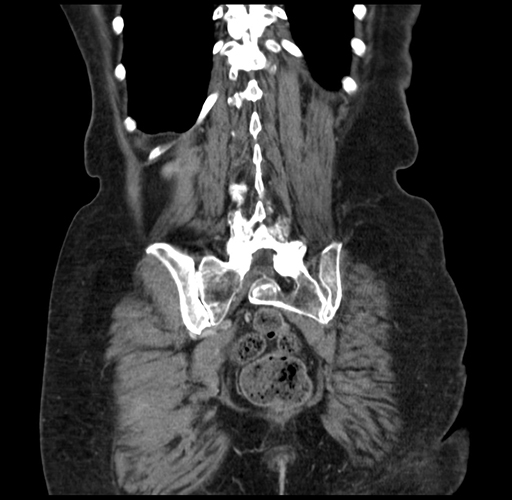

Pre-Chemo: Coronal Venous

Coronal Venous